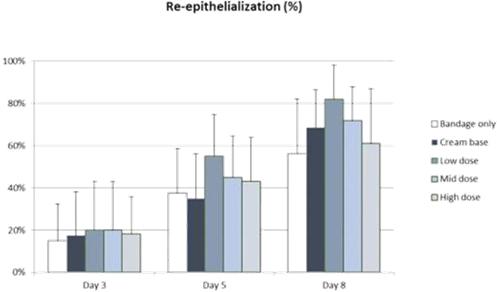

In addition to relief of symptoms, inflammation, pain, and others, we believe INM-755 may impact the underlying disease by enhancing skin integrity in a subset of EB patients. We have completed more than 30 preclinical pharmacology and toxicology studies to investigate the effects of CBN. Several of these nonclinical studies explored the effect on important symptoms such as pain and inflammation. In in vitro pharmacology studies, CBN demonstrated activity in reducing markers of inflammation. CBN upregulated expression of a type of keratin called keratin 15, or “K15”, which might lead to skin strengthening and reduced blister formation in EB simplex, or “EBS”, patients with mutations in another keratin called keratin 14, or “K14”. The anti-inflammatory activity of CBN may be beneficial in healing chronic wounds caused by prolonged inflammation. Following a review of our toxicology studies, the Netherlands National Competent Authority and Ethics Committee approved the initiation of a Phase I clinical study in healthy volunteers. We have safety data with INM-755 cream in 22 healthy adult volunteers from our first Phase I study (755-101-HV) in which subjects had the INM-755 cream applied to their upper backs daily for 14 days. An interim safety analysis of the first 16 subjects was reviewed by the Netherlands National Competent Authority and Ethics Committee and determined to be adequate to allow initiation of the second Phase I study testing INM-755 cream on small wounds. That second study has completed and we now have safety data for INM-755 cream applied to small open wounds daily for 14 days in 8 healthy adult volunteers.

In preclinical pharmacology studies, CBN demonstrated activity as an anti-inflammatory and antinociceptive agent. CBN upregulated expression of keratin 15 (K15), which might lead to skin strengthening and reduced blister formation in EBS patients with keratin 14 (K14) mutations. At the cream concentrations chosen for clinical development, it does not appear to impede wound healing of partial-thickness wounds. Its anti-inflammatory activity may be beneficial in healing chronic wounds caused by prolonged inflammation.